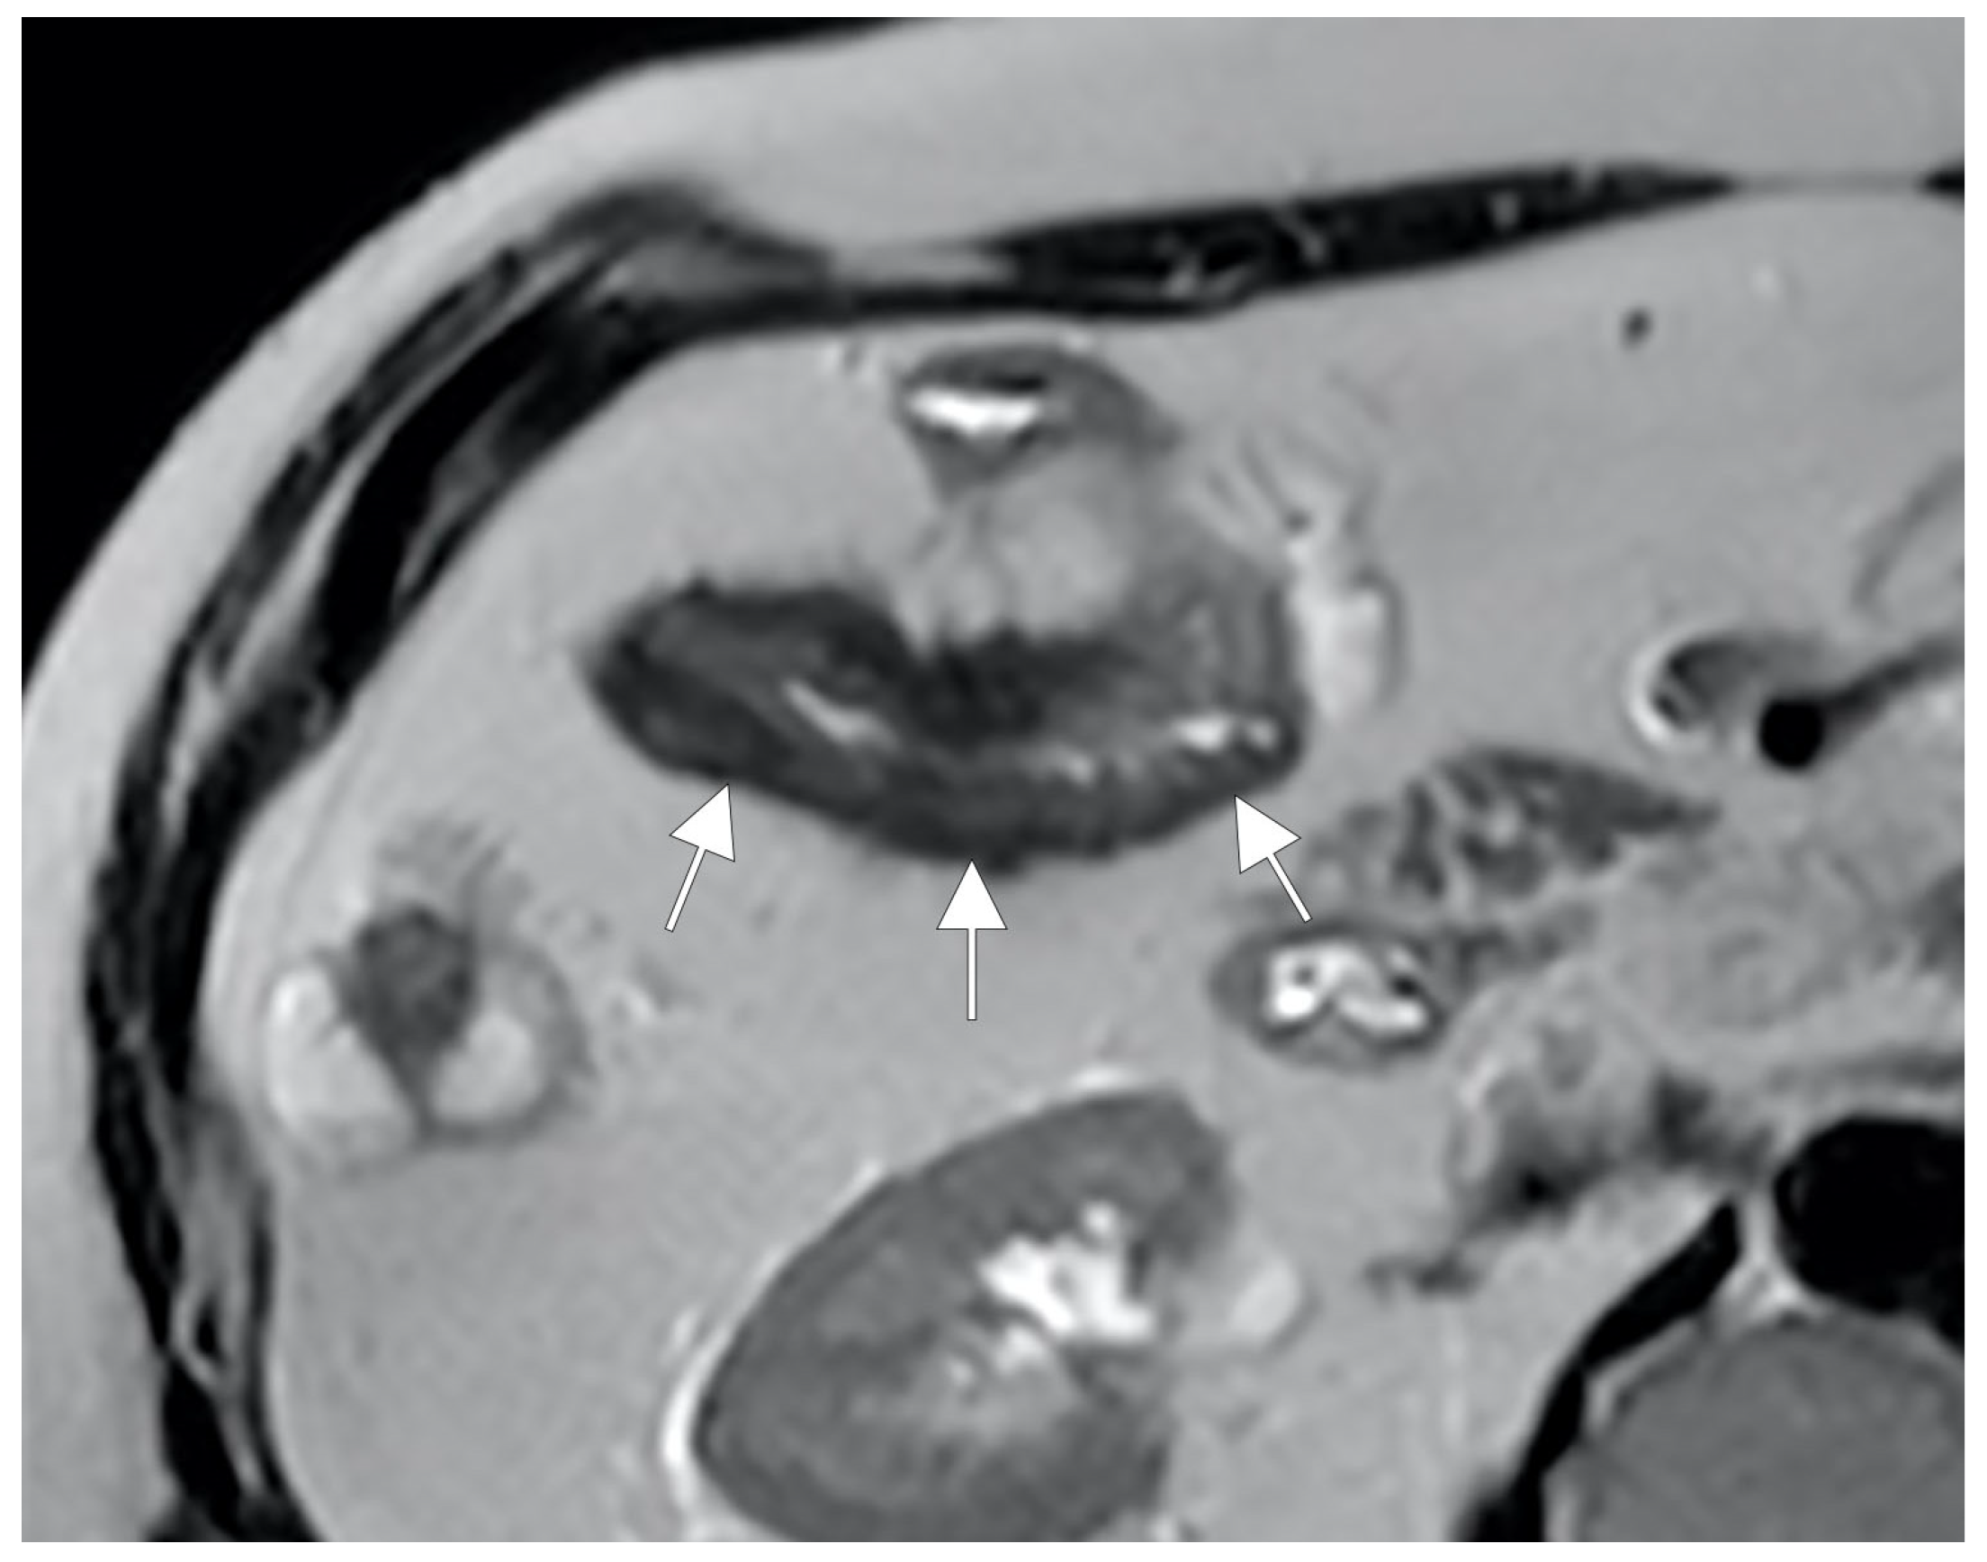

Another possible imaging findings of mesenteric inflammation is an abscess that appears as the usual appearance of an encapsulated collection with a rim enhancement and/or a central zone containing air or necrotic material. Moreover, MRE may show perienteric edema/inflammation as a high T2-W signal or a restricted diffusion in the mesenteric fat adjacent to abnormal bowel loops and the engorged vasa recta that supply an inflamed bowel loop (“comb sign”) [6] (Figure 15).

Figure 15.

During the active phase, the vascularization of the mesenteric fan increases with an evident engorgement of the vasa recta that takes on the appearance of a clear palisade that stands out against the background of the hypertrophic mesentery. According to some, this aspect commonly resembles the teeth of a hair comb (comb sign) but which we like to imagine instead, due to the thickness of the hypertrophic vasa recta, as a palisade of a fence (mesentery fence). (A,B,D,E): Coronal fast imaging employing steady-state acquisition (FIESTA) image, (C): coronal contrast-enhanced fat-suppressed T1-weighted maximum intensity projection image, and (F): coronal contrast-enhanced fat-suppressed T1-weighted image show engorgement of the vasa recta (yellow arrowheads in (A–F) images.